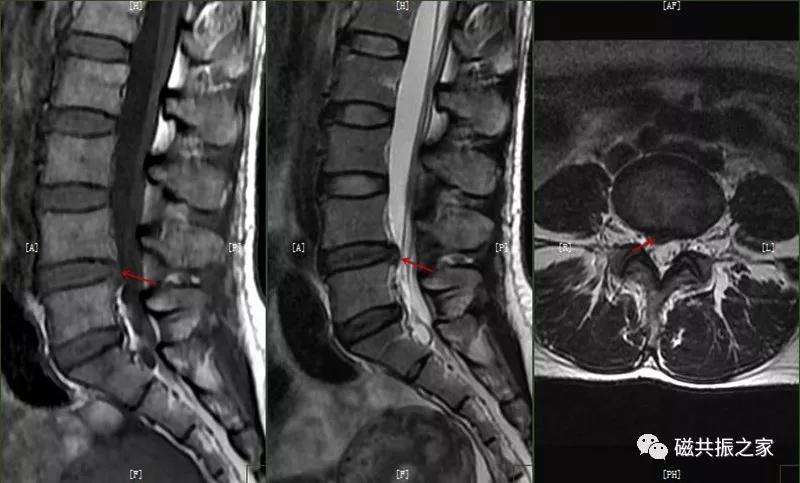

7.腰椎椎体滑脱

脊椎滑脱是指椎体相对下一节椎体向前或后方滑动移位,颈椎、腰椎常见。腰椎以4/5椎体和腰/骶连接部常见。滑脱分为向前和向后滑脱,根据上下椎体的滑动距离分为四度(在矢状位上将椎体上缘分为4等分,对应着1-4度滑脱)。